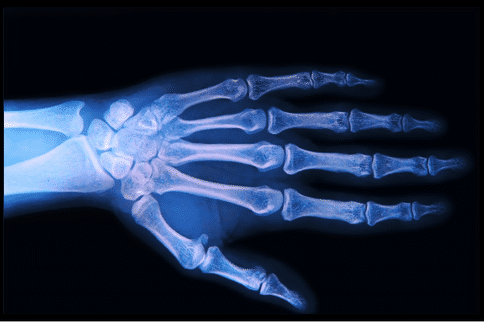

为了实现这一目标,詹姆斯、克莱门斯和他们的同事们研究了尺骨应力性骨折的老鼠,尺骨是相当于人类手臂两根骨头中较细和较长的一块前肢骨。